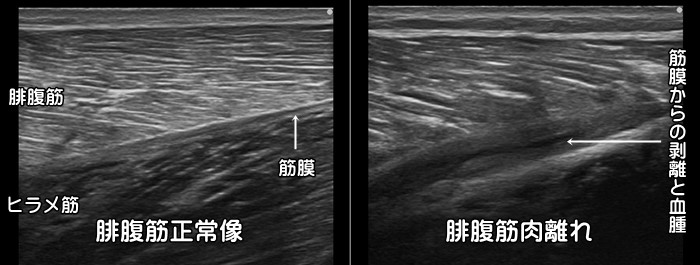

ふくらはぎ・腓腹筋の肉離れ

急なダッシュ動作やスピード練習で発症します。中高年に好発します。多くはふくらはぎの腓腹筋の内側に発症します。筋線維が途中で断裂するのではなく、筋肉を包む筋膜から剥がれるように損傷します。剥離した部分には血腫が見られます。通常肉眼での皮下出血は受傷から2~3日後に確認できます。